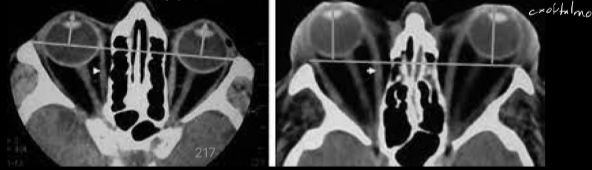

Tc exoftalmos

A

TC

- protusion ocular anormal

- disociacion indice globo ocular

Estudio imagen Orbitopatia tiroidea

Agrandamiento bilateral de musc extraoculares

- TC: abordar enf no complicada

- RM: decidir tx y ver compromiso del n.optico